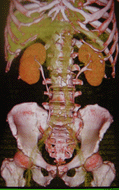

三次元像 |

|